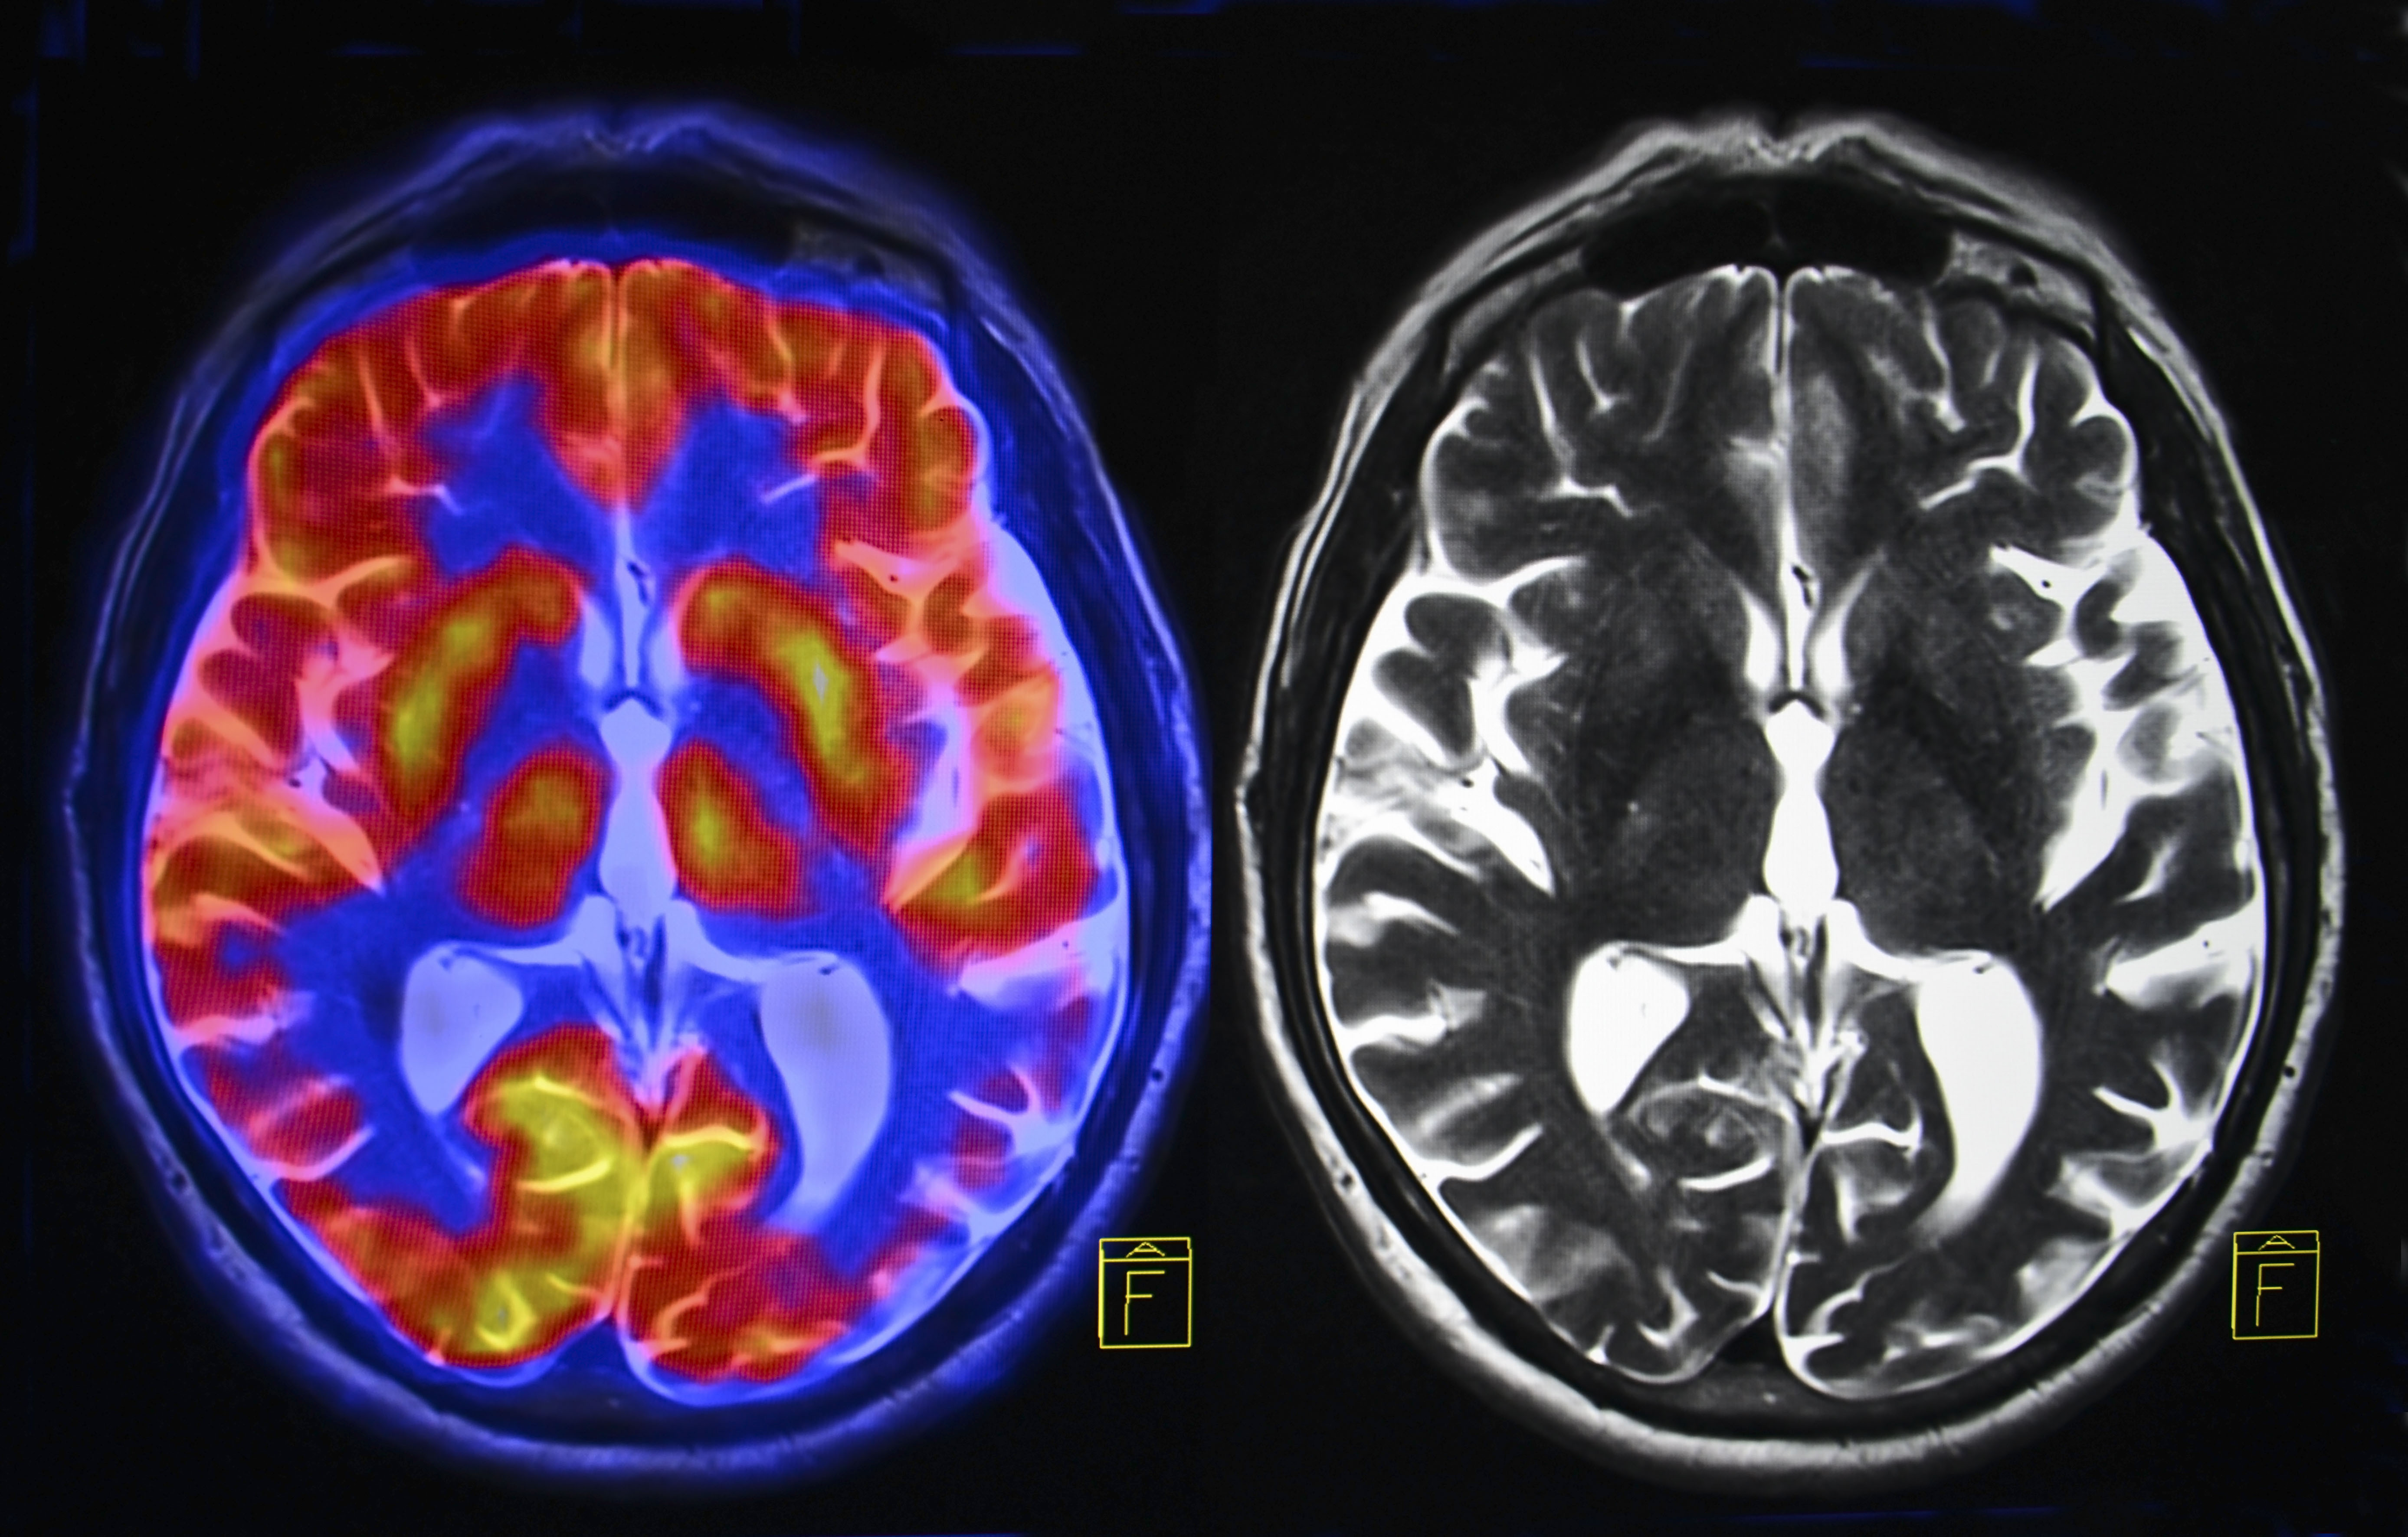

MADRID – Las complicaciones

neurológicas de la covid-19 pueden incluir delirio, daño nervioso, derrames y

un raro tipo de inflamación cerebral, aunque los investigadores no tienen

claro, en este último caso, si es producto del coronavirus o de la reacción

inmunitaria, según un estudio que publica la revista Brain.

Según la investigación,

“parece” que, debido a la pandemia, está aumentando la prevalencia de

una “rara y a veces mortal” afección inflamatoria, la

encefalomielitis diseminada aguda (ADEM), indica un comunicado del UCL.

De entre todos los pacientes,

doce presentaron inflamación cerebral y, de ellos, nueve sufrieron ADEM, una

afección que normalmente se ve en niños y que puede desencadenarse por

infecciones virales.

El SARS-Cov-2 no fue detectado

en el líquido cefalorraquídeo de ninguno de los pacientes del estudio, lo que

“sugiere que el virus no atacó directamente al cerebro para causar la

enfermedad neurológica”, indica a nota.

Pero en algunos pacientes, sí

encontraron pruebas de que la inflamación del cerebro estaba

“probablemente causada” por una respuesta inmunológica a la

enfermedad, lo que “sugiere que algunas complicaciones neurológicas de la

covid-19 podrían provenir de la respuesta inmunológica, más que del propio virus”.